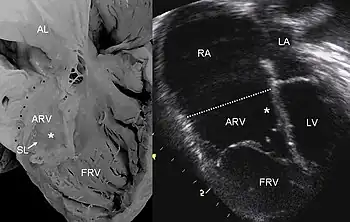

| Pathological specimen and ultrasound image of a heart with Ebstein's anomaly: Abbreviations: RA: right atrium; ARV: atrialized right ventricle; FRV: functional right ventricle; AL: anterior leaflet; SL: septal leaflet; LA: left atrium; LV: left ventricle; asterisk: grade II tethering of the tricuspid septal leaflet | |